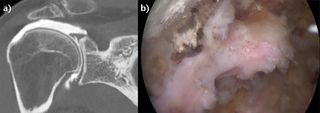

A coronal view of a right shoulder computed tomography (CT) arthrogram shows a probable B2 rotator cuff lesion with a Patte 3 retraction. b) The arthroscopic view through lateral portal revealed after partial debridement that the tendon was not retracted but actually had adhered under the acromion. Reproduced from Lädermann et al.,28 with permission.